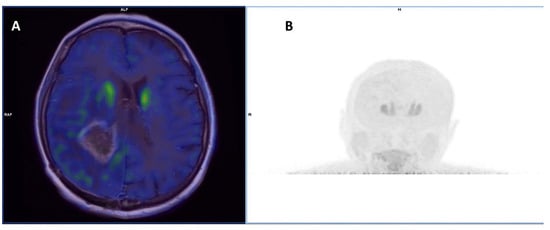

- Kebir, S.; Rauschenbach, L.; Galldiks, N.; Schlaak, M.; Hattingen, E.; Landsberg, J.; Bundschuh, R.A.; Langen, K.-J.; Scheffler, B.; Herrlinger, U.; et al. Dynamic O-(2-[18F]Fluoroethyl)-L-Tyrosine PET Imaging for the Detection of Checkpoint Inhibitor-Related Pseudoprogression in Melanoma Brain Metastases. Neuro. Oncol. 2016, 18, 1462–1464. [Google Scholar] [CrossRef] [PubMed]

| Kebir et al. [45] | 2016 | R | [18F]-FET | melanoma | 5 (NR) | To evaluate pseudoprogression in patients treated with ICI | TBRmax was higher in patients with true progression (5.4 vs. 2.5), as well as time to peak was significantly shorter (17 min vs. 45 min) |